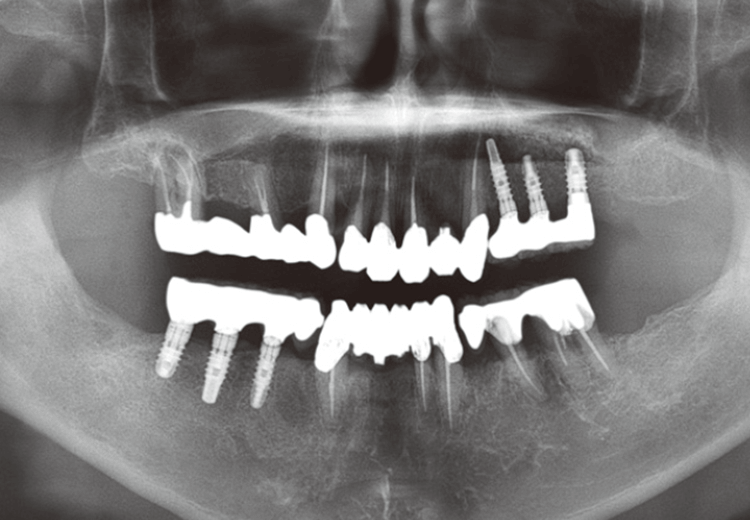

図3 初診時パノラマ写真。全顎的な治療が必要と考えられた。

図12 治療終了時のパノラマ写真。長期的に維持すsるためには今後のメインテナンスが重要になる。